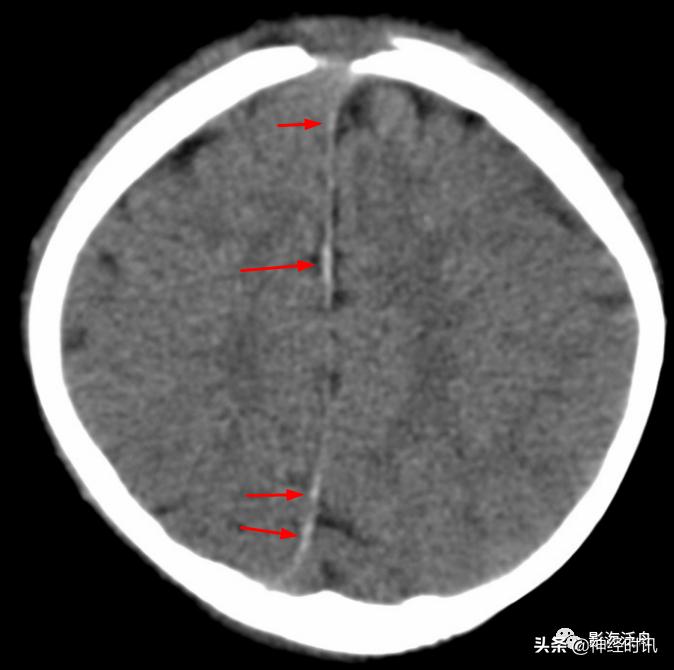

红箭所指的大脑镰局部呈连续的长条状高密度影,容易被误诊为少量蛛血,此系大脑镰局部不完全钙化所致。注意观察密度增高的大脑镰边缘非常光滑、且居中(红箭),与少量蛛血形成的偏密征、边缘毛糙等征象恰好相反。

间断性的大脑镰不完全线状钙化(红箭),同样呈边缘光滑、居中改变。